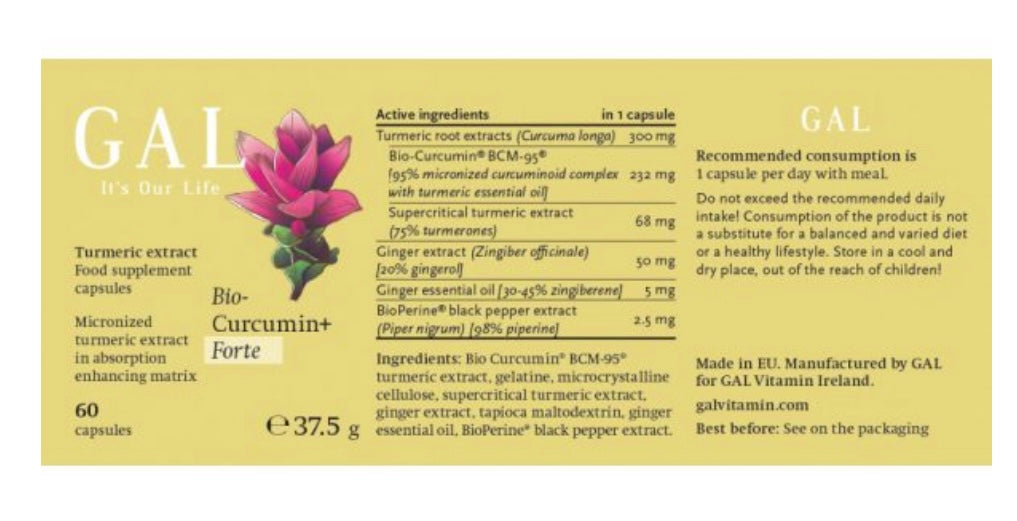

Bio-Curcumin+ Forte capsule

It has to be noted that, Bio-Curcumin® in itself elevates blood curcumin levels highly effectively, and it can cross the blood-brain barrier as the above-mentioned studies demonstrate clearly. We further increased its effectivity, as we have combined it with other methods to help absorption. As an extra to Bio-Curcumin®, our product is infused with large amounts of turmeric essential oil, ginger extract, ginger essential oil and BioPerine® welcome additions. We are not aware of any other product that combines all of the available methods to promote the absorption of turmeric.